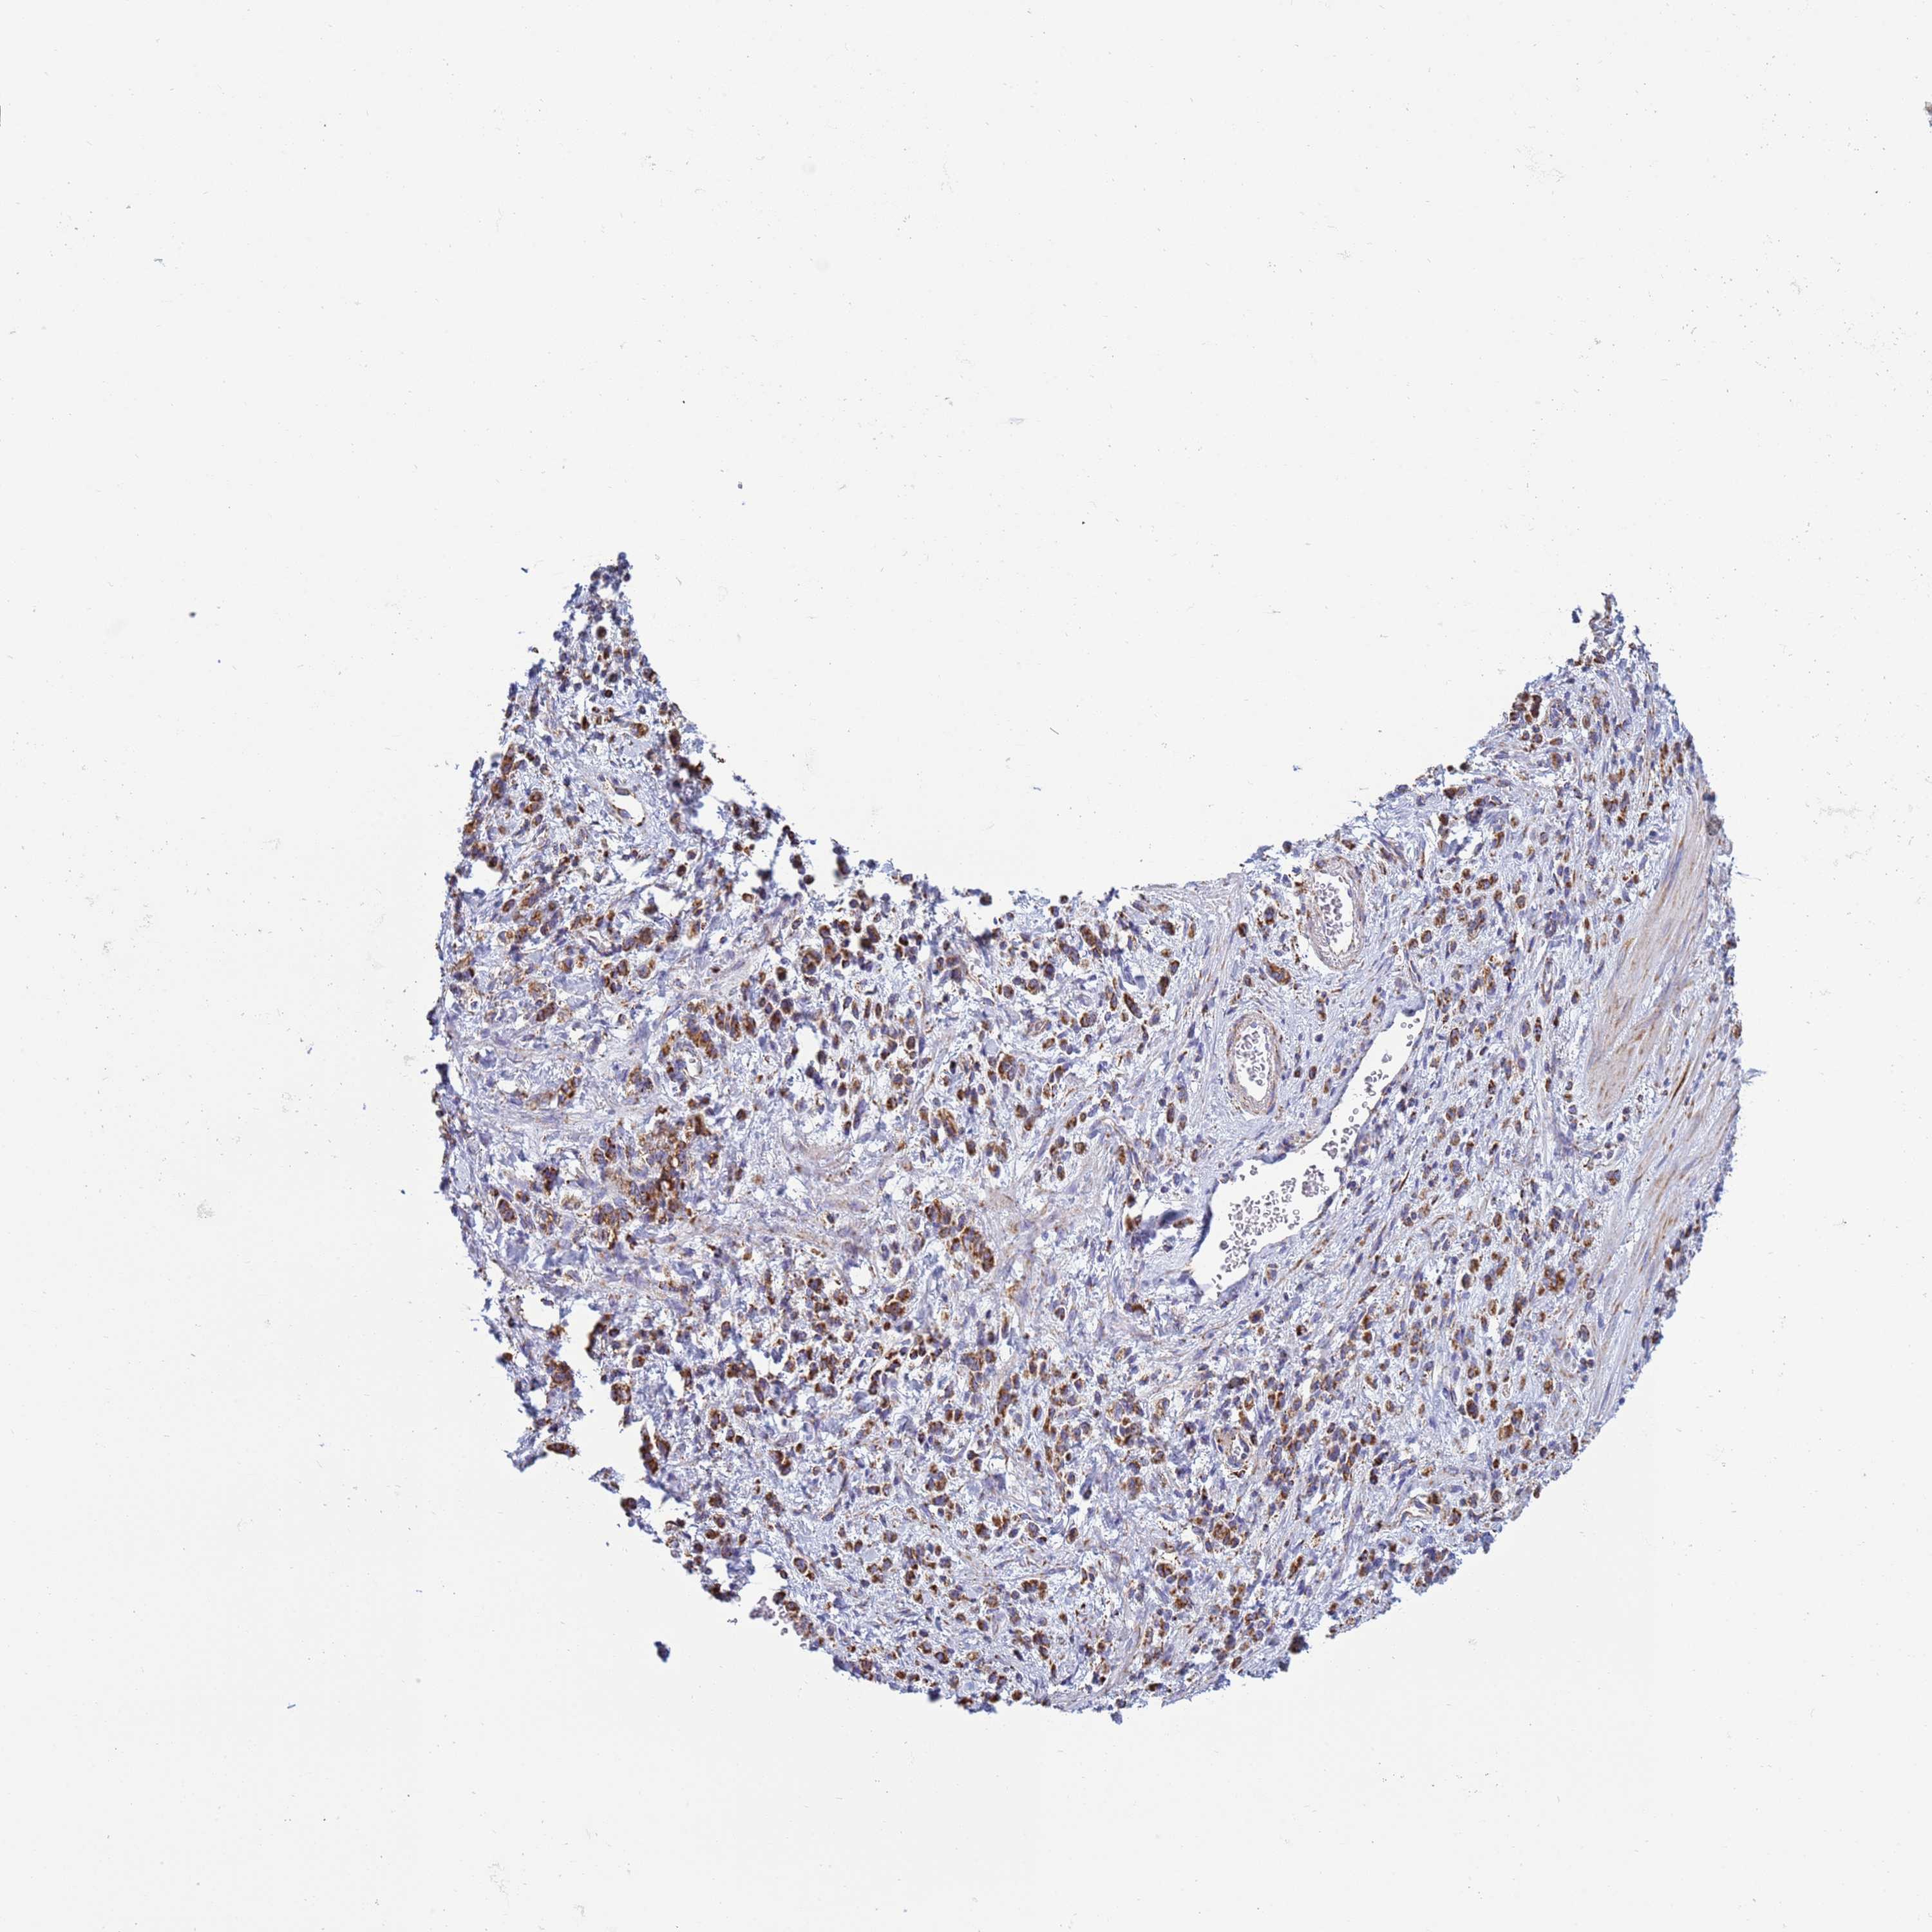

STOMACH CANCER - Protein expressioni

A mouse-over function shows sample information and annotation data. Click on an image to view it in a full screen mode. Samples can be filtered based on level of antibody staining by selecting one or several of the following categories: high, medium, low and not detected. The assay and annotation is described here.

Note that samples used for immunohistochemistry by the Human Protein Atlas do not correspond to samples in the TCGA dataset.

Antibody stainingi

Antibody staining in the annotated cell types in the current human tissue is reported as not detected, low, medium, or high, based on conventional immunohistochemistry profiling in selected tissues. This score is based on the combination of the staining intensity and fraction of stained cells.

Each image is clickable and will lead to virtual microscopy that enables deeper exploration of all samples and also displays staining intensity scores, fraction scores and subcellular localization as well as patient and tissue information for each sample.

Antibody HPA042945

Staining

High

Medium

Low

Not detected

Intensity

Strong

Moderate

Weak

Negative

Quantity

>75%

75%-25%

<25%

None

Location

Nuclear

Cytoplasmic/membranous

Cytoplasmic/membranous,nuclear

Adenocarcinoma, NOS